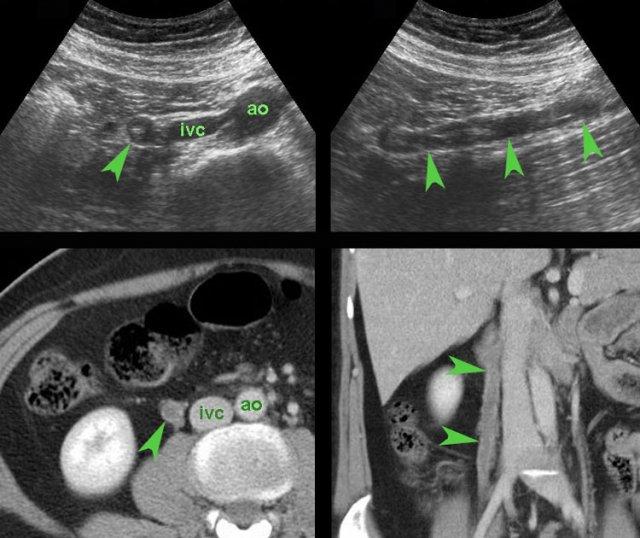

Bẫy chẩn đoán: nang buồng trứng phải không triệu chứng ở phụ nữ bị viêm ruột thừa. (V= tĩnh mạch chậu)

Ca lâm sàng 6

Ở người phụ nữ trẻ này, một nang buồng trứng phải xuất huyết nổi bật (đầu mũi tên) được phát hiện và ban đầu được cho là nguyên nhân gây ra các triệu chứng ở hố chậu phải.

Tuy nhiên, thăm khám thêm cho thấy hình ảnh viêm ruột thừa cấp (mũi tên).

Nang buồng trứng là phát hiện tình cờ, không có triệu chứng.